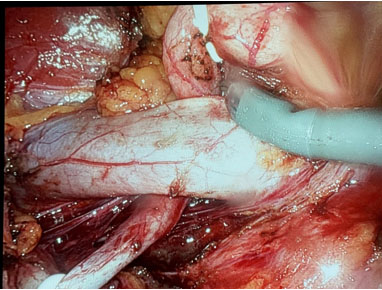

A 34-year-old male was referred for incidental right hydronephrosis observed on a CT abdomen and pelvis after a motor vehicle collision. The patient reported right flank pain following the accident. Past medical history and past surgical history were unremarkable. The patient denied hematuria, dysuria, lower urinary tract symptoms, or a history of urinary tract infections. Right costovertebral angle tenderness was present on physical examination. Urinalysis and urine culture were negative. Serum creatinine was 1.17 mg/dL, down from a previous measurement months before the motor vehicle accident of 1.77 mg/dL. A CT urogram revealed severe right hydronephrosis with possible ureteropelvic junction obstruction and diffuse thinning of the right renal parenchyma (Figure 1A and Figure 1B). A diuretic renogram was then obtained due to the thinning of the renal parenchyma and an unknown duration of hydronephrosis on the right kidney. There was a concern that the renal function may have declined over time due to prolonged obstruction. Subsequent diuretic nuclear renogram demonstrated normal uptake and a dilated right renal collecting system with delayed response to Lasix consistent with right partial high-grade obstruction (t1/2 25 minutes) (Figure 2). We then proceeded with cystoscopy with right retrograde pyelography to better detail the origin of the obstructive process. This demonstrated a tortuous proximal ureter with medial deviation and severe hydronephrosis consistent with a retrocaval ureter (Figure 3). The additional investigation using a retrograde pyelogram was performed for better diagnostic testing in case of future intraoperative planning for correction of the ureter. The retrograde pyelogram added details on the course of the proximal ureter and its’ anatomical tortuosity. A ureteral stent was placed for symptomatic relief of obstruction. The patient elected to undergo right robotic-assisted laparoscopic ureteroureterostomy. The patient was given prophylactic antibiotics. He was placed in the left lateral decubitus position with table flexion. Standard 8 mm da Vinci Xi (Intuitive Surgical, Sunnyvale, CA) trocar placement was performed for a right renal procedure (Figure 4). The robotic portion began with medial reflection the hepatic flexure and exposure of the right renal pelvis in standard fashion. The renal pelvis was expectedly dilated and prominent. The proximal ureter and IVC were identified. The ureteropelvic junction was dissected and encircled with a vessel loop. The ureter was found to be coursing posterior to the IVC, confirming retrocaval ureter. Identification of the ureter distal to the level of obstruction on the medial side of the IVC in the interaortocaval space was conducted (Figure 5). The distal aspect of the ureter was isolated with a second vessel loop. Care was taken not to unduly devascularize the ureter while mobilizing it to the extent allowing for transection and transposition of the ureter ventral to the IVC. The proximal ureter was sharply transected just distal to the ureteropelvic junction. The previously placed ureteral stent was removed. The ureter was transposed anterior to the IVC without tension (Figure 6). The proximal and distal ends of the ureter were spatulated, and a standard ureteroureterostomy was performed with two running stitches of 4-0 PDS suture (Ethicon, Bridgewater, NJ). Prior to completion of the ureteral anastomosis, a new 6 French, 28 cm double-J ureteral stent was then advanced antegrade over a Sensor wire (Boston Scientific, Marlborough, MA). The proximal stent coil was placed into the renal pelvis, and the anastomosis was completed. A JP drain was placed, and a Foley catheter was kept indwelling.

Figure 5: Identification of the ureter distal to the level of obstruction on the medial side of the IVC in the interaortocaval space.

Share Image: